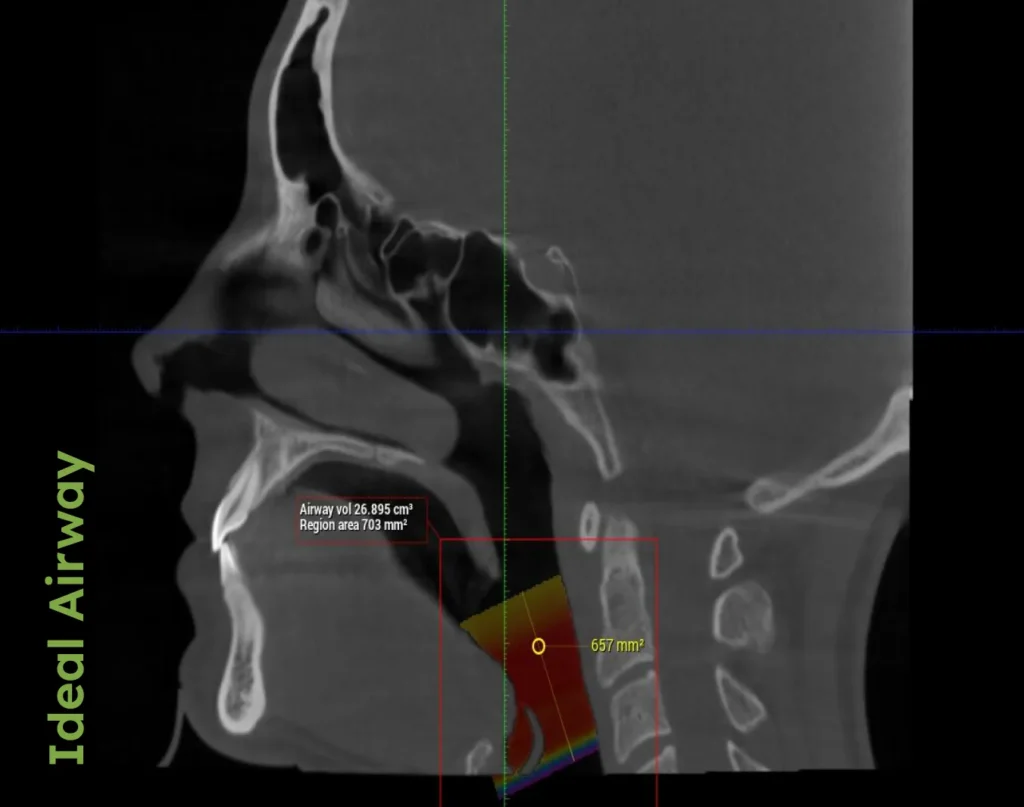

In his book AIM, Dr. Porter explains how traditional orthodontics, primarily focused on straightening teeth, often overlooks the critical aspect of airway health. Conventional orthodontic approaches can pull the front teeth backward, inadvertently narrowing the airway and leading to problems such as habitual mouth breathing and snoring—both clear indicators of potential airway compromises.

Adults with airway problems may experience chronic snoring, daytime sleepiness, or difficulty breathing at night. These symptoms necessitate comprehensive evaluations to manage and treat underlying airway issues effectively.

• Palatal Expansion: Often the first stage in adult orthodontics for those with compromised airways, this technique helps to widen the upper jaw, improving nasal breathing and serving as a foundational step before aligning teeth.